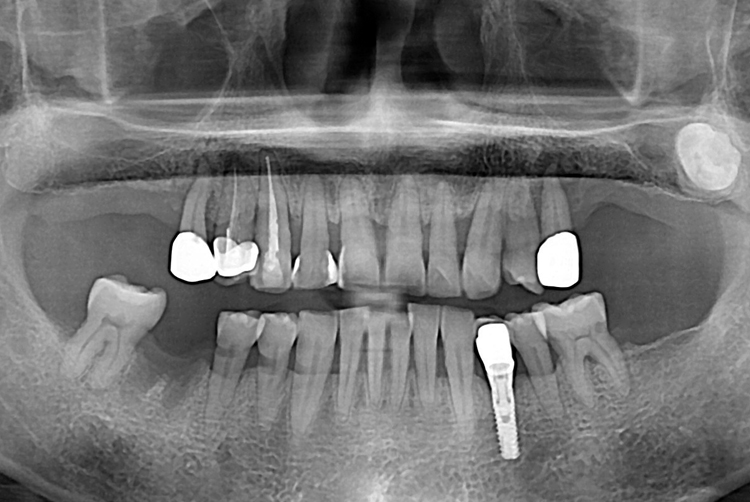

1383 이정호_후.jpg

치료후 : 2019-12-20

세종치과는 많은 환자와 다양한 케이스를 바탕으로 항상 편안한 임플란트 수술을 제공하고자 노력하고,

오래동안 튼튼히 쓸 수 있는 임플란트 수술을 가장 큰 목표로 삼고 있습니다